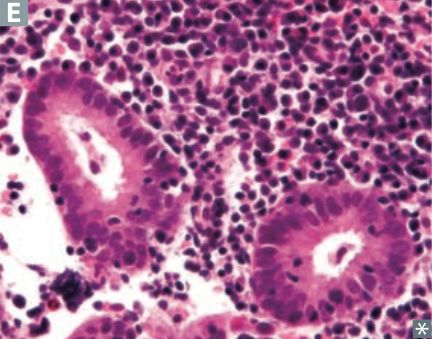

The histology image below has lymphocytes and plasma cells in the endometrium, which is indicative of _____